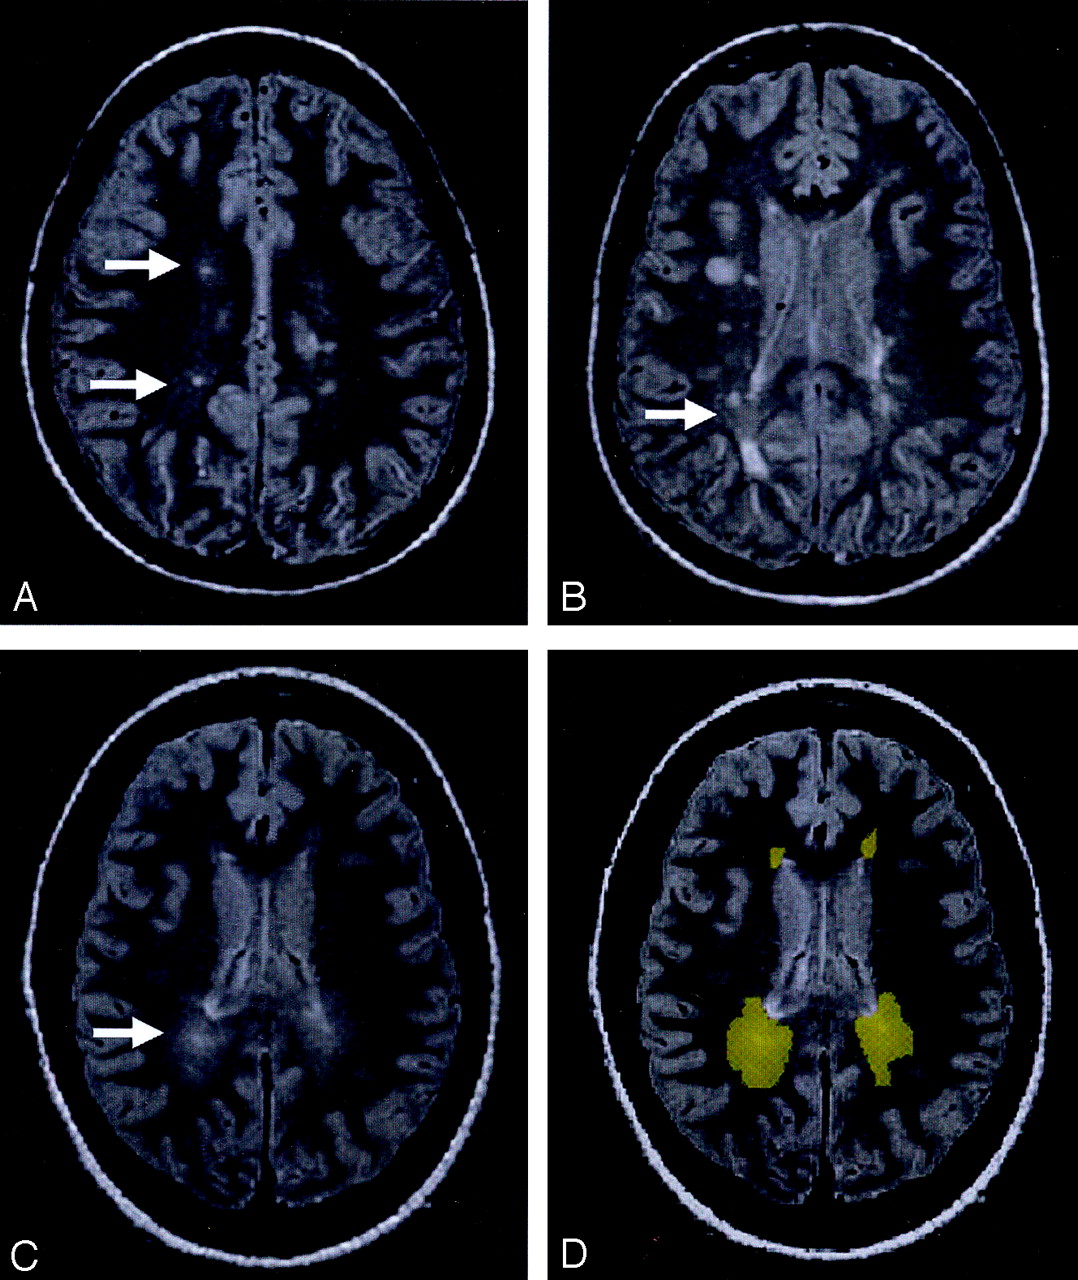

The PD-weighted scan shows DAWM areas, which are typically located in the periventricular and centrum semiovale regions of white matter in MS patients.

A, DAWM with a single plaque.

B, DAWM with several plaques.

C, pure DAWM without plaques visible.

D, outlined DAWM masks from C.

Most DAWM areas were located in periventricular and centrum semiovale regions. As shown in Figure 1, these DAWM areas can have a single (Fig 1A) or several lesion plaques (Fig 1B) embedded or attached, or have no visible T2 plaques (Fig 1C). The average volume of DAWM (mean ± SD: 18.3 ± 11.4 mL) was greater than that of T2 lesion plaques (mean ± SD: 11.0 ± 10.8 mL), which showed significant difference (P = .04) and indicated the quite extensive and diffuse nature of DAWM; however, the volume of NAWM from selected areas does not represent the total NAWM and therefore is not meaningful for volume comparison with DAWM.